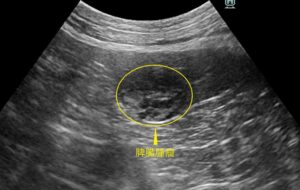

腹部超音波検査

肝臓や胆嚢、脾臓、腎臓、副腎、膀胱、消化管、リンパ節、前立腺などを確認し、形態や大きさの異常やしこりなどの有無をチェックします。

9歳の柴犬の子が、わんにゃんドックの腹部超音波検査で脾臓に1.5cm大のしこりが見つかりました。症状はありませんでしたが、脾臓の腫瘤は悪性腫瘍の可能性もあるため、後日脾臓摘出術を行いました。摘出した脾臓腫瘤の病理検査は結節性過形成で、幸い腫瘍ではありませんでしたが、結節性過形成は大きくなると破裂して腹腔内出血を起こすことがあります。今回は健康診断で早期に脾臓腫瘤が発見できたことで、腹腔内出血もせず早期に治療を行うことができました。